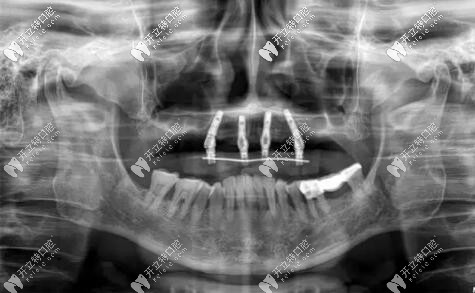

惠先生種植方案:前期ALL-ON-4即刻負(fù)重,后期上頜竇外提升,同期植入兩顆種植體,做ALL-ON-6,馬龍一體橋。

目前已完成ALL-ON-4即刻負(fù)重,通過手術(shù)情況來看,效果確實(shí)比較好,作為一位地道老陜?nèi)?,惠先生的感激之情溢于言表?/p>